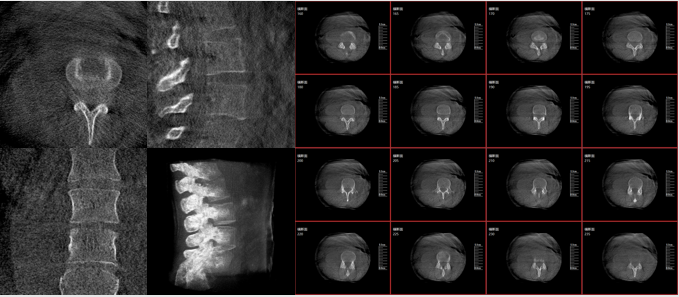

術中三維影像

而三維影像的MPR圖像組可以通過不同平面的切分,使成像區內更豐富的信息得以呈現。尤其是二維影像無法涉及的橫斷面,提供了另一個空間維度的信息量。

在MPR圖像中,冠狀面、矢狀面和橫斷面的信息大大提高了醫生對于病灶區以及手術效果的判定。